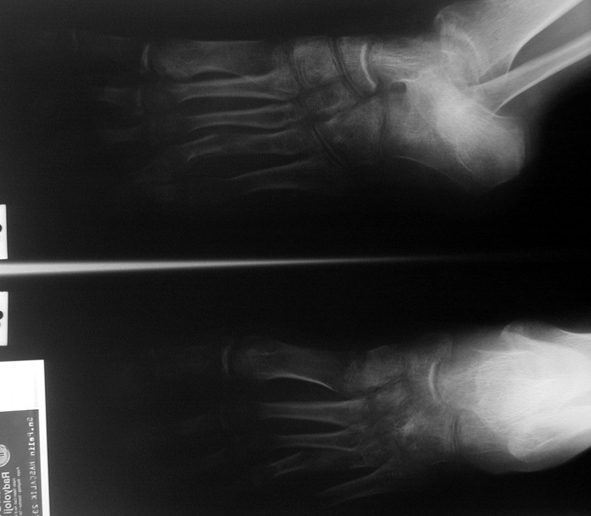

El parmağı (metakarp) ve ayak parmağı (metatars) kısalıkları doğuştan tek başına, geniş bir sendrom grubuyla birlikte, travma sonrası, Freiberg hastalığı (avasküler nekroz) sonrası görülebilir.

Doğuştan metakarp ve metatars kısalığının görülme sıklığı 1/1000’den azdır. Kadınlarda erkeklere göre 5 kat daha fazla görülür ve sıklıkla (%72) iki taraflıdır. En sık 4. parmak tutulur. Bu tür olgularda sorunun nedeni tam olarak bilinmemekle brlikte deformitenin genellikle epifiz plağının erken kapanmasından kaynaklandığı düşünülmektedir.

Metakarp kısalığında kozmetik görünümün bozulması ve dominant elin kullanımı sırasında yorulma, metatars kısalığında ise kozmetik haricinde metatarsalji, kısa parmağın dorsale kayması sonucu deformite oluşması, plantar yönde açılanması sonucu ağrı ve bası ülserleri, ve ayakkabı giymede zorluk nedeniyle ameliyat gerekebilir.

Doğuştan metakarp ve metatars kısalıklarının redavisi için pek çok teknik tanımlanmakla birlikte en çok akut uzatma sonrası kemik uçlarına greft konması ve distraksiyon osteogenezi (kallotasis) kullanılmaktadır. 1 cm.den daha fazla uzatma gereken olgularda kallotasis yöntemi önerilmektedir. Kliniğimizde de metatars ve metakarp uzatma için unilateral eksternal fiksatör ve sirküler eksternal fiksatör yardımıyla distraksiyon osteogenezi yöntemi tercih edilmektedir.